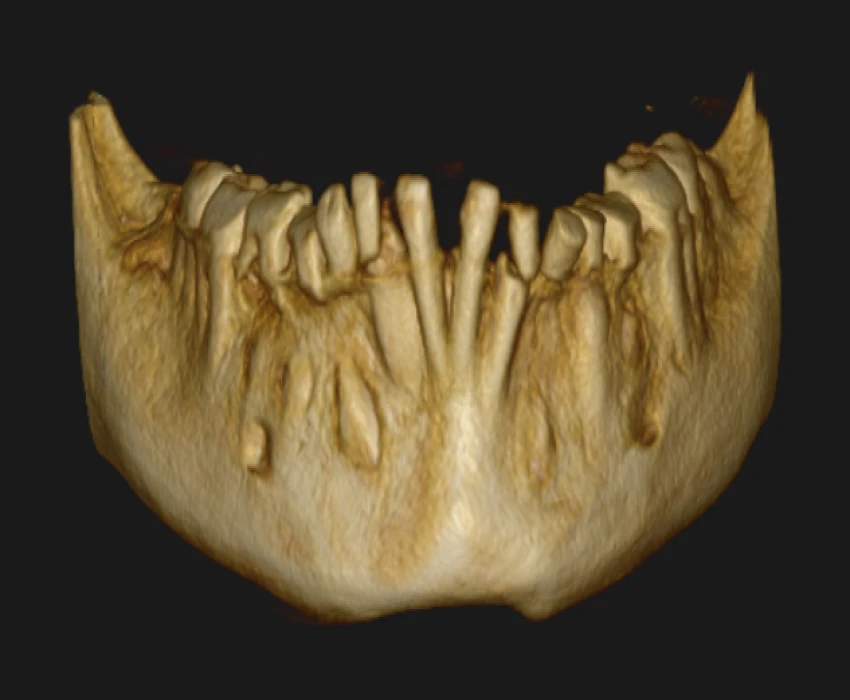

On intra-oral examination generalized loss of cervico-occlusion height and colour of the teeth appeared opalescent and brown in colour.

On the basis of history, clinical examination, and radiographic investigation final diagnosis was given as Amelogenesis imperfecta- Hypoplastic Type.

In patients with hypoplastic amelogenesis imperfecta, the basic alteration centers on inadequate deposition of enamel matrix. In the generalized pattern, pinpoint-to-pinhead–sized pits are scattered across the surface of the teeth and do not correlate with a pattern of environmental damage. The buccal surfaces of the teeth are affected more severely. Both dentitions, or only the primary teeth, may be affected. All of the teeth may be altered, or only scattered teeth may be affected.